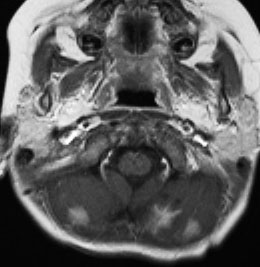

典型的な小脳虫部(小脳の真ん中)の髄芽腫です。横の方,ルシュカ孔へ伸びていないので上衣腫と区別できます。ガドリニウムという造影剤で白く写っています。